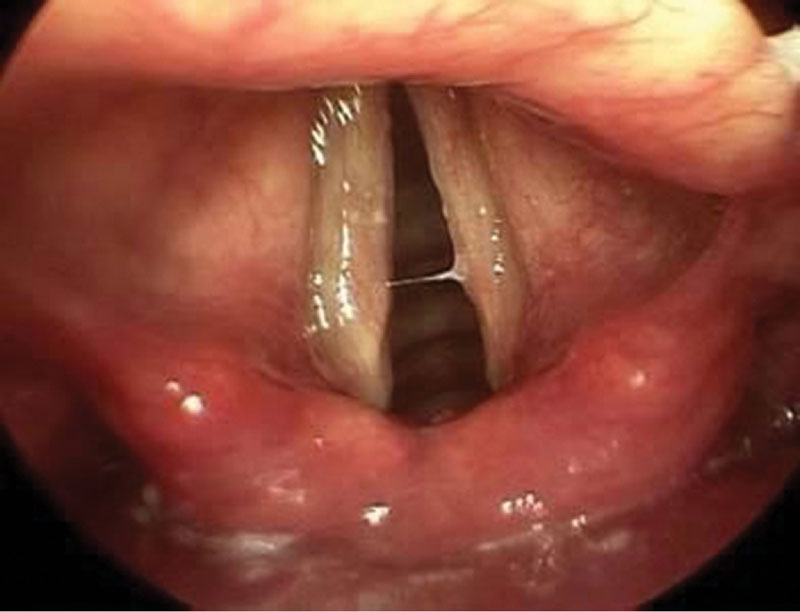

Рис. 3. ЭГДС на аппарате Olympus EVIS EXERA III (CV-190), осмотр и заключение Л.И. Телятниковой: недостаточность кардии, Hill-3; эрозивный рефлюкс-эзофагит, степень В по Hoshihara; дуоденогастральный рефлюкс; рефлюкс-гастрит с тотальным поражением желудка

Пациент, 34 года, с восьмилетним анамнезом изжоги, которую он купирует антацидами, альгинатами. Один-два раза в год принимает ИПП (омепразол, эзомепразол, рабепразол) курсами в течение четырех недель, а также эпизодически «по требованию». За последний год трижды проходил лечение у оториноларинголога в связи с тонзиллитом (чувство першения в горле, осиплость голоса при отсутствии заложенности носа, повышение температуры). После выполнения ларингоскопии (рис. 2) оториноларингологом были рекомендованы консультация гастроэнтеролога и эндоскопическое исследование. Проведена видеоэзофагогастродуоденоскопия (рис. 3) аппаратом экспертного класса (Olympus EVIS EXERA III  (CV-190).